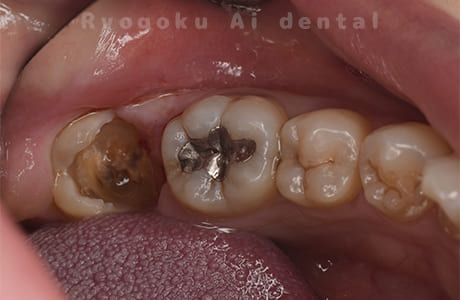

Case10

- 右下6番 重度カリエス

- 右下8を右下6へ移植に自家歯牙移植

- 約1か月半

- 220,000円

右下の銀歯が外れかかっているとのことでご来院された患者様です。虫歯が大きく、かつ歯が割れており、保存不可能と判断し、親知らずの移植を行いました。